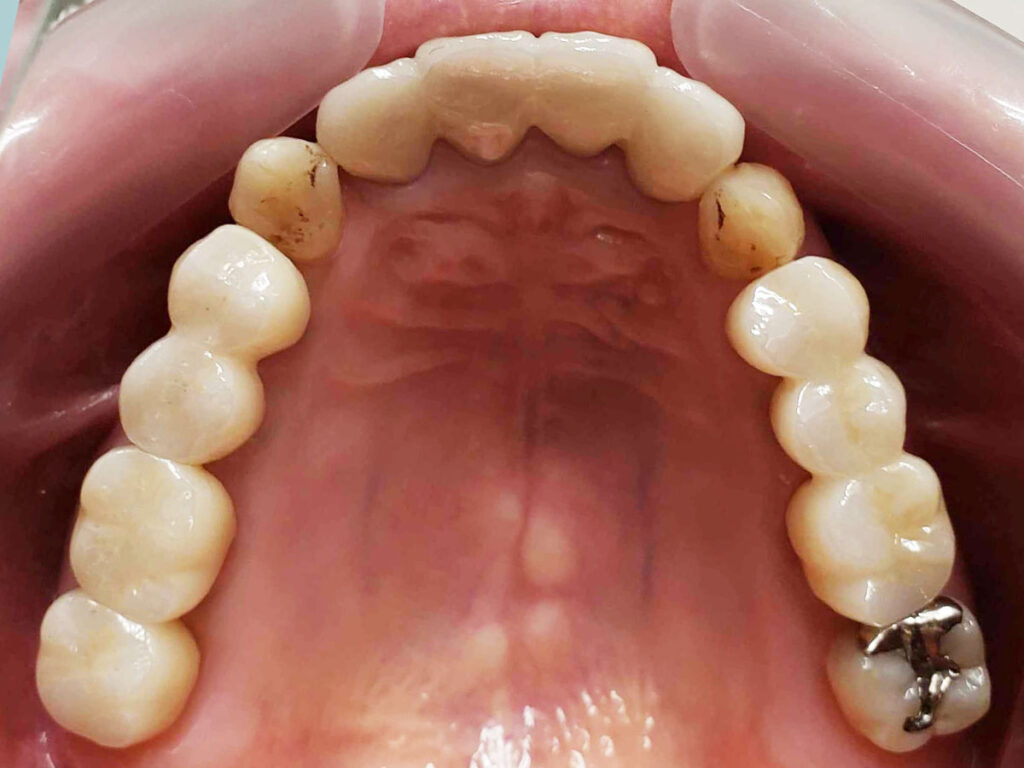

術後1年後

歯磨き等の管理は言うことなしですね。夜間のマウスピースも着用されているとの事で、素晴らしいの一言に尽きます。1回も遅刻なし、予約変更なしに遠方から1時間かけて約2年来院された方なので、私的にも感無量、満足といった所ですかね。